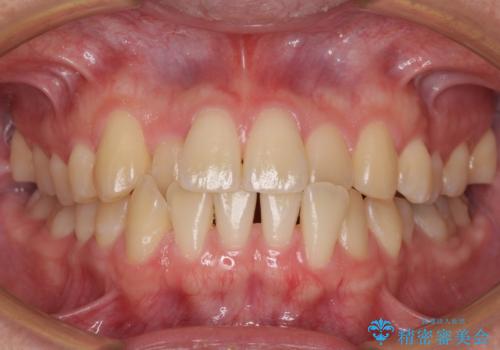

30代女性 前歯のがたつき